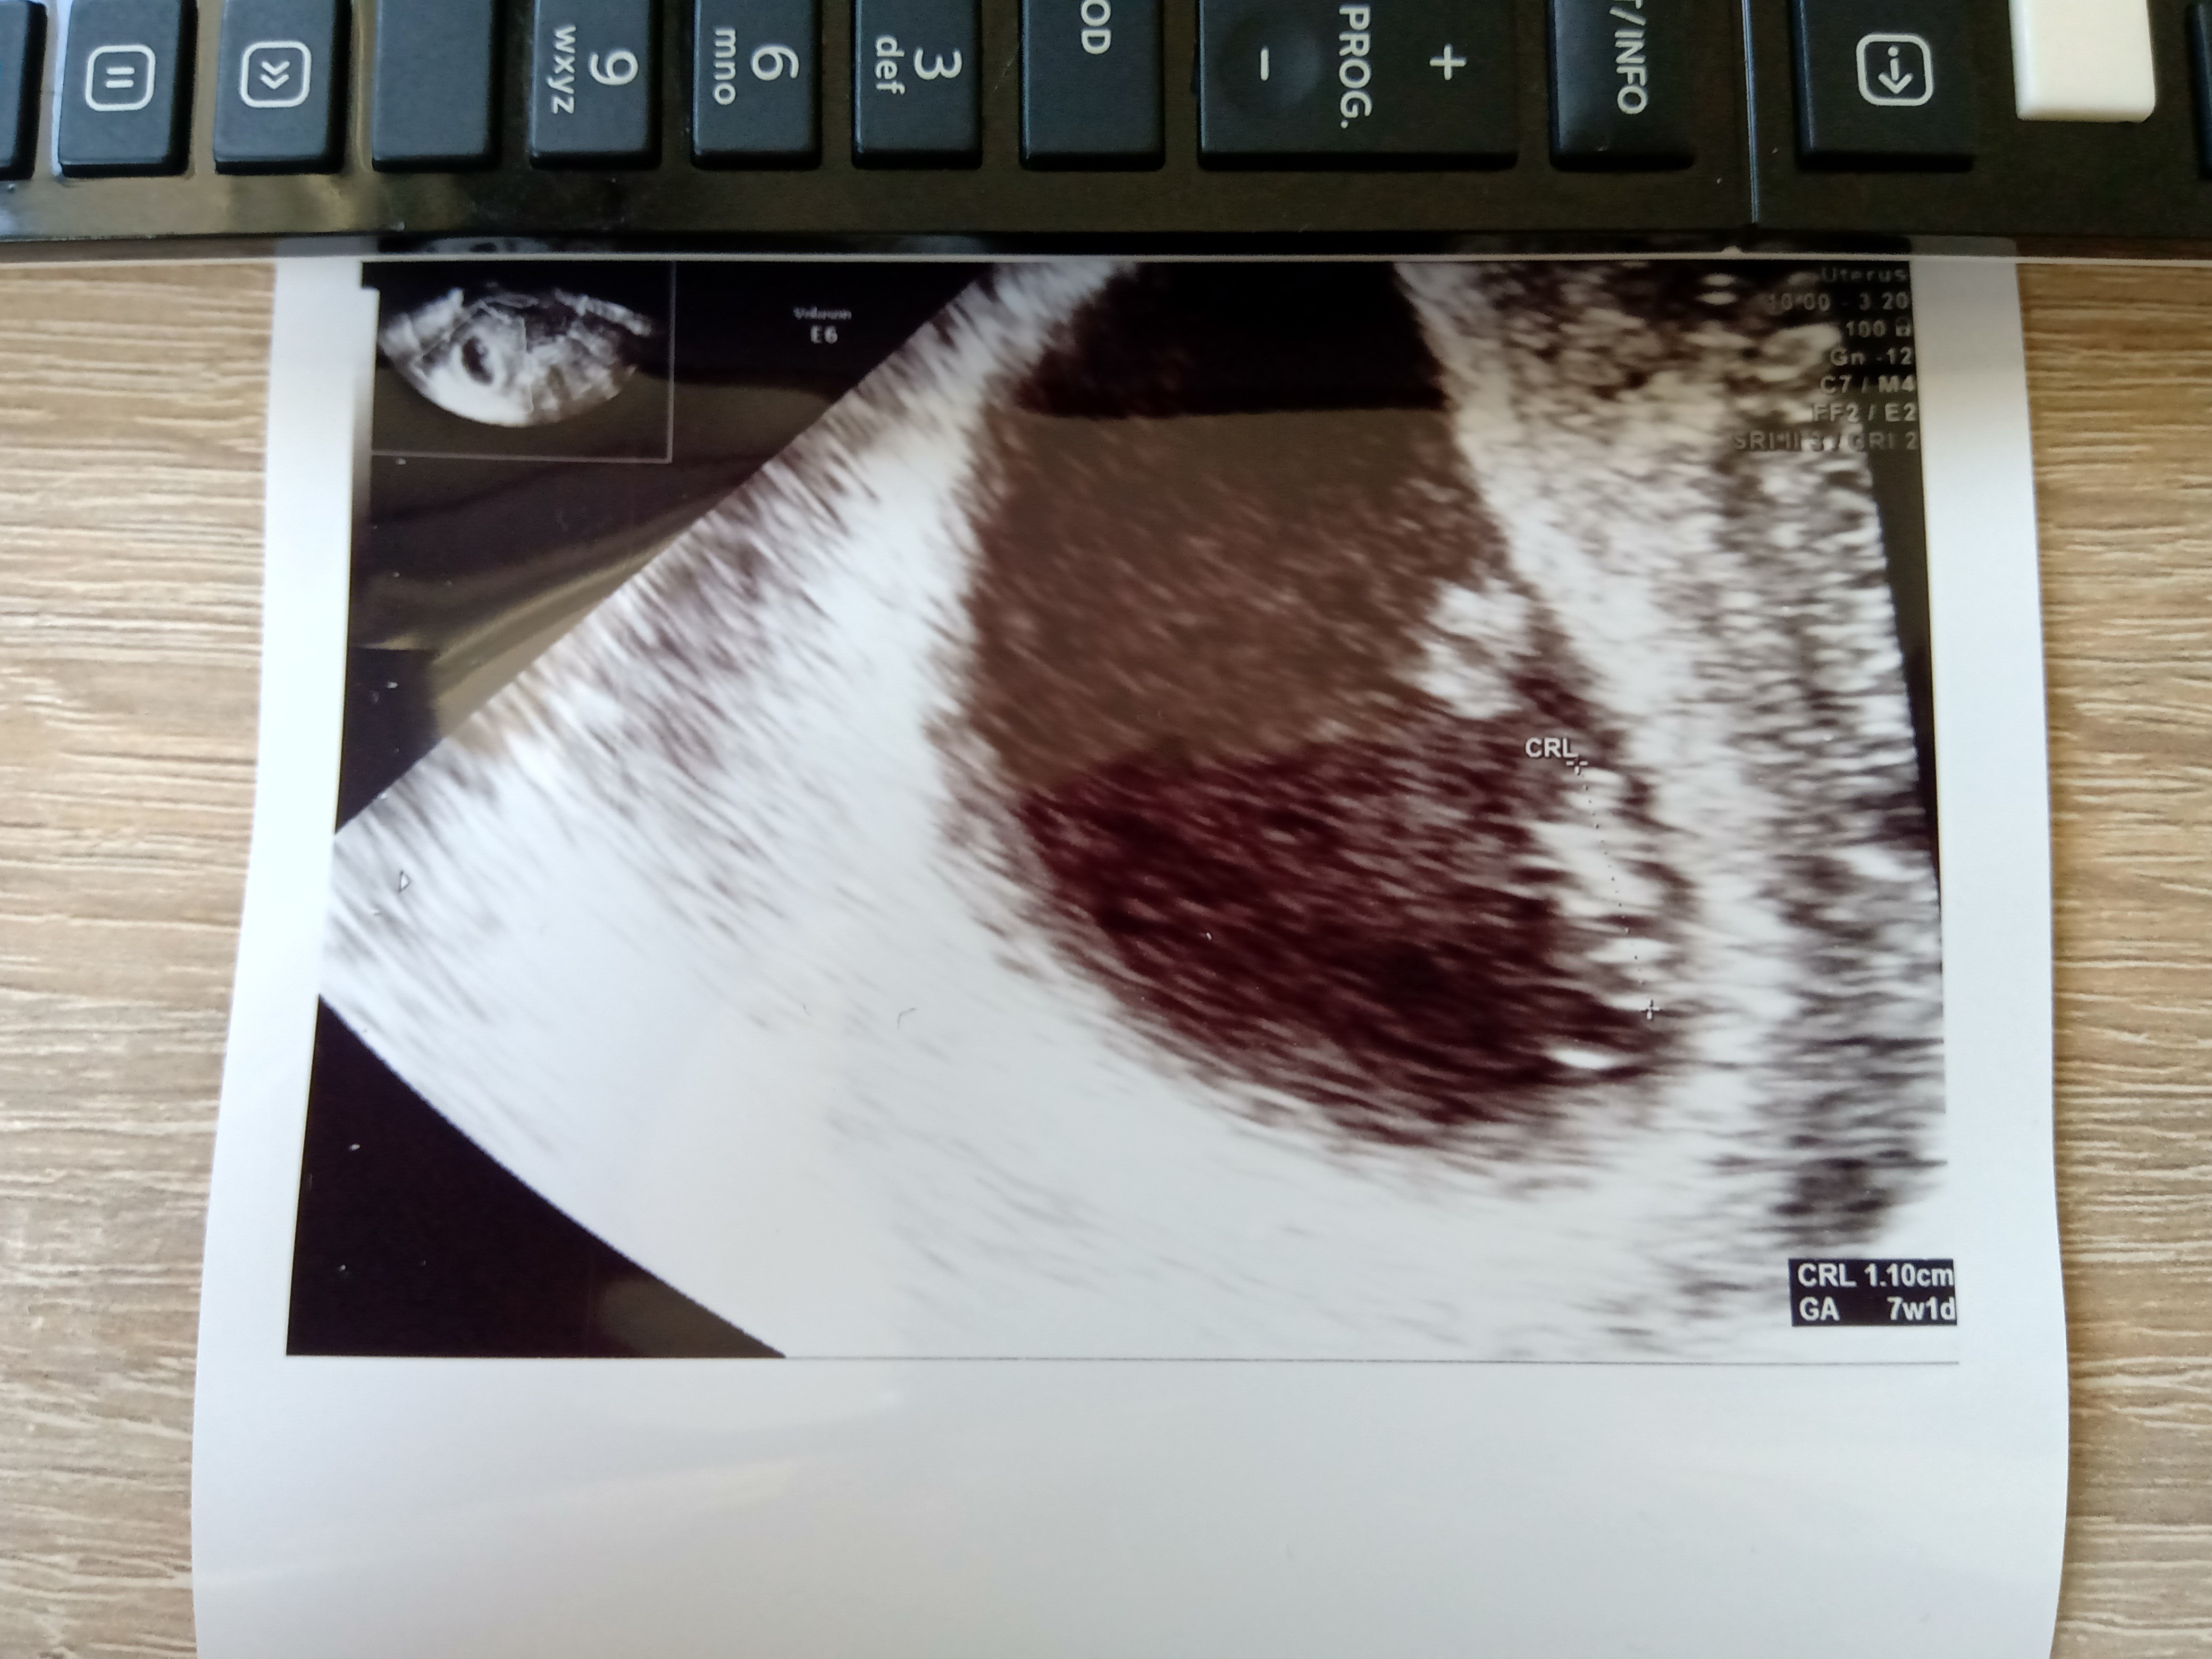

Nie pochwaliłam się jeszcze wczorajszą wizytą. Więc serduszko jest, młode ma już 1cm wzrostu. Kolejna wizyta za 2 tygodnie. Wcześniej wyniki, ten cały "powitalny" zestaw za 300zł.

Chciałam wyprosić luteinę, bo miałam 2x kilkudniowe plamienia ale jednak lekarz poraz kolejny mi przypomniał, że luteina to nie panaceum. 90% powodów poronień to wady zarodka i tu progesteron nie pomoże.

Na szczęście obecnie nie plamię ale jakoś czuję, że jeszcze to wróci. Doktor mówi, że jeśli wróci, to wtedy będziemy się martwić a na razie ciąża jest prawidłowa.

Myślę sobie, że te moje plamienia mogły wynikać z dźwigania starszego synka. Teraz staram się go nie podnosić, jak nie muszę i obecnie jest spokój.